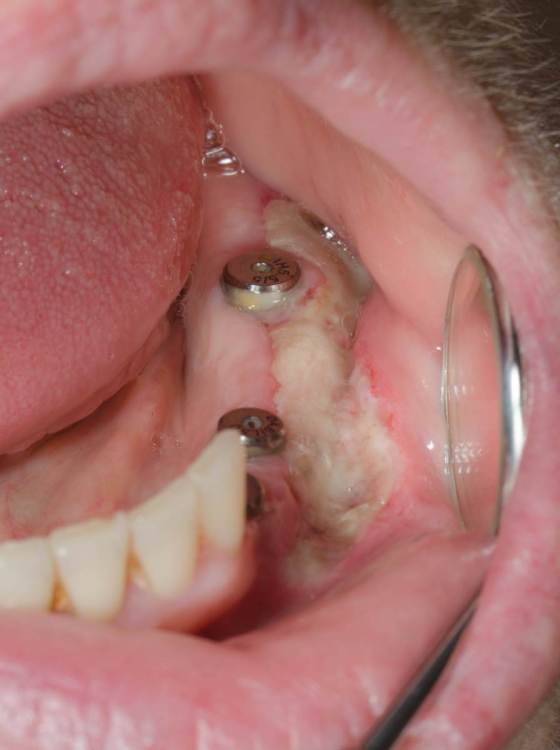

1722472141_5.thumb.jpg.5e93a924b4d15ee1e8ef646bc90b2c32.jpg

Примерно через 3 года после снятия МК коронок  (клык не снимал, не требовалось). Насколько я понимаю ССТ все же дал рост и кератинизировалася.